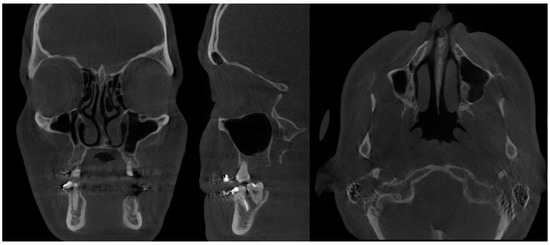

- Type 2 in-pure SSS (iSSS) (Figure 3, Figure 4 and Figure 6) related to maxillary deformation (might be related to maxilla-mandibular skeletal class II/III deformities or others), clinically asymptomatic, not related to trauma or surgery, 1–3 MS walls retracted, OMC clear, no opacification, like suggested by Lee et al., the “not so silent sinus” [18];